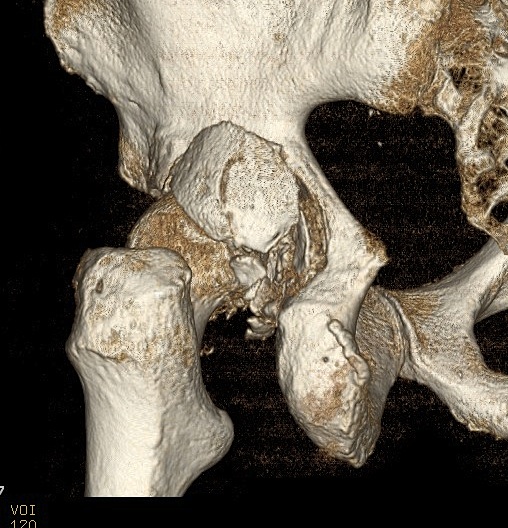

3. Screen for retained fragments

Compulsory CT

- xray will not detect fragments < 2mm

Remove / ORIF depending on size of fragment and location / Pipkin type

Non-concentric Reduction

Esssential to obtain X-ray and CT after reduction

X-ray

- head - teardrop distance must equal contralateral side

CT

- only with CT can < 2mm fragments be seen